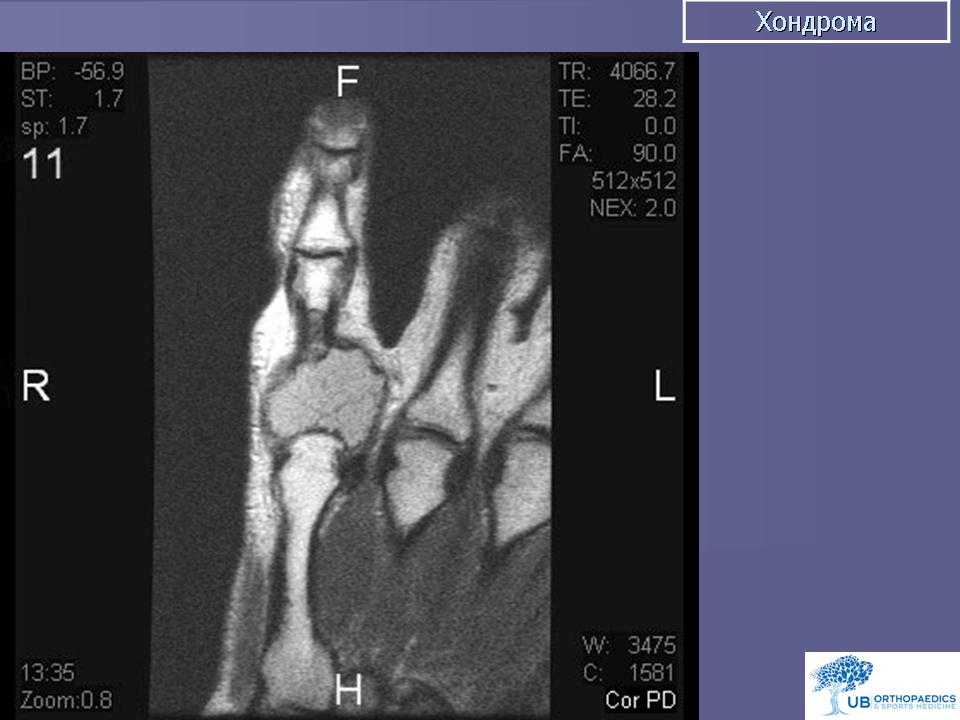

Хондрома. Встречается одинаково часто у лиц обоего пола, как правило, в возрасте 7-20 лет. Наиболее часто локализуется в костях кистей и стоп, но встречается также в костях таза, ребрах и длинных трубчатых костях. Хондромы составляют 10-15% от всех доброкачественных опухолей костей. Малигнизация хондром отмечается в 5% случаев. Хондромы могут быть одиночными и множественными. Если опухоль располагается внутри кости, ее называют энхондромой, на поверхности кости - экхондромой. В детском возрасте заболевание обычно протекает латентно. Клиническая картина бывает различной при энхондромах и экхондромах. Энхондромы характеризуются вначале при небольших размерах, бессимптомным течением, а затем в связи с ростом опухоли и давлением на корковый слой возникают боли. С течением времени боли усиливаются, появляется припухлость. При пальпации определяется плотная болезненная неподвижная по отношению к кости опухоль. Довольно частым осложнением бывает патологический перелом. При экхондроме ведущим начальным симптомом является наличие пальпируемой плотной опухоли, а также деформация пораженной части скелета. По достижении опухолью больших размеров наблюдаются симптомы нарушения функции близлежащих органов и тканей, особенно выраженные при опухолях костей таза. Диагностика хондром основывается на клинической картине и данных рентгенологического исследования. При экхондромах на рентгенограммах определяется участок уплотнения на фоне мягких тканей. Как правило, в этом участке видны очаги обызвествления, дающие крапчатый рисунок. В зависимости от степени обызвествления конфигурация опухоли на рентгенограммах выявляется более или менее четко. Основной рентгенологический симптом при энхондромах - изменения костной структуры. Степень их бывает различной в зависимости от выраженности процессов деструкции и обызвествления. Обычно в центре вздутого участка кости определяется одиночный очаг равномерного просветления, имеющий округлую или овальную форму и четкие контуры, резко отграниченный от неизмененной кости. На фоне просветления обнаруживаются крапчатые или хлопьевидные пятнистые тени, соответствующие очагам обызвествления хряща. В случаях, когда процессы деструкции слабо выражены, просветление может отсутствовать, кость представляется пятнисто разреженной, а в центральной части поражения видны конгломераты обызвествлений. Лечение хирургическое: при опухолях мелких костей и ребер - удаление пораженной кости, при хондромах костей таза - удаление опухоли с резекцией кости, при хондромах длинных трубчатых костей - резекция пораженного участка кости с одномоментным замещением дефекта трансплантатом. Важно тщательно соблюдать принцип абластики в ходе операции, поскольку клетки хондромы обладают большой способностью имплатироваться.

Хондрома. Хондромы, как указывает С. А. Рейнберг, наблюдаются преимущественно в детском и юношеском возрасте По данным Т. П. Виноградовой, возраст больных различен с преобладанием со второго по четвертое десятилетие жизни. Из 52 наблюдаемых нами больных хондромой большая половина была в возрасте 30—40 лет. Преобладание какого-либо пола среди больных не отмечается. В большинстве случаев поражаются короткие трубчатые кости кисти (примерно в 70% случаев), реже — стоп, затем кости таза, отростки позвонков, грудина. Длинные трубчатые кости поражаются весьма редко. В длинных трубчатых костях хондрома локализуется в метаэпифизарных концах. По данным И. Г. Лагуновой (1962), в среднем и пожилом возрасте хондрома в длинных трубчатых костях располагается в метафизе, распространяясь в эпифиз или диафиз. В наших наблюдениях превалировала метаэпифизарная локализация хондром. В детском возрасте хондромы в длинных трубчатых костях, как правило, поражают метафиз. В коротких трубчатых костях кисти и стопы хондромы чаще бывают множественными, причем отмечается двустороннее поражение. В плоских костях, и особенно в длинных трубчатых костях, наблюдаются солитарные хондромы. Суставы, как правило, не изменены. Но при больших размерах опухоли наступает выраженная деформация костей, механически препятствующих движениям в суставах.

Рентгенологическая картина энхондром довольно характерна. Определяются округлой и овальной формы очаги деструкции костной ткани. Эти очаги деструкции располагаются или центрально, вызывая вздутие кости, или эксцентрично. На хрящевом фоне могут выделяться одиночные костные перемычки и вкрапления извести. В ряде случаев эти известковые вкрапления бывают множественными, сливаются между собою и как бы заполняют весь хрящевой фон (очаг деструкции). Кортикальный слой неравномерно истончен, местами утолщен, не прерывается. В длинных трубчатых костях очаг деструкции, располагаясь в метаэпифизарном отделе, вызывает умеренное вздутие кости. Истонченный кортикальный слой, как правило, имеет ровные контуры. Возможна булавовидная деформация пораженного отдела кости. Вследствие поражения эпифизарных хрящей у детей может наблюдаться торможение роста кости в длину. Наблюдаются патологические переломы пораженной кости.